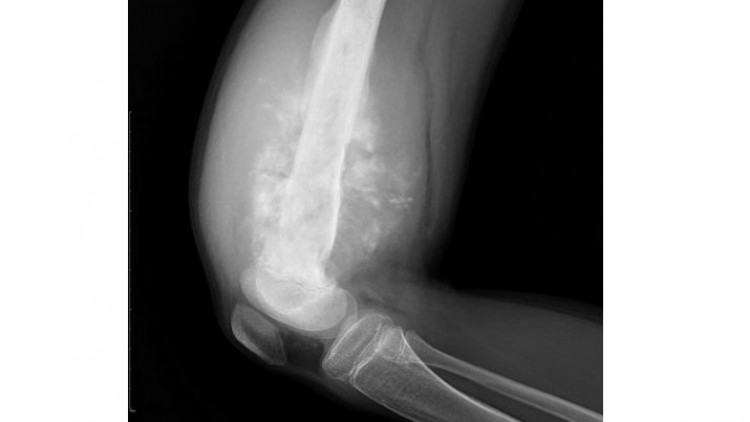

นายแพทย์ณรงค์ อภิกุลวณิช รองอธิบดีกรมการแพทย์และโฆษกกรมการแพทย์ เปิดเผยว่า เนื้องอกกระดูก คือ ภาวะที่เซลล์ของกระดูกมีการแบ่งตัว เจริญเติบโตผิดปกติโดยไม่ทราบสาเหตุ ทำให้กระดูกถูกทำลายไป หรือมีก้อนโตขึ้นอย่างผิดปกติ เนื้องอกชนิดธรรมดา (ไม่ร้าย) ที่เกิดภายในกระดูก แบ่งเป็น 3 ระยะ คือ ระยะที่ 1เนื้องอกมีขนาดเล็ก ไม่มีอาการปรากฏ ติดตามดูอาการก่อนได้ ระยะที่ 2 เนื้องอกเริ่มทำลายกระดูกบางส่วน มีอาการปวดตามตำแหน่ง ระยะที่ 3 เนื้องอกทะลุกระดูกออกมาภายนอกกล้ามเนื้อและเป็นก้อนโตขึ้น ซึ่งจะทำให้ปวดรุนแรงขึ้น ส่วนเนื้องอกชนิดร้ายหรือมะเร็งของกระดูกยังแบ่งได้เป็นสองชนิด ชนิดแรก มีต้นกำเนิดโรคจากตำแหน่งอวัยวะอื่น แต่แพร่กระจายมายังกระดูก เช่น จากปอด ตับ หรือเต้านม เป็นต้น มักเป็นในผู้ป่วยในอายุ 40 ปีขึ้นไปและมีประวัติเป็นโรคมะเร็งอื่นมาก่อน อาการที่พบได้แก่ ปวด หักง่ายแม้เป็นอุบัติเหตุเล็กน้อย กระดูกผิดรูป หรือคลำเจอก้อนเป็นต้น ส่วนอีกชนิดคือมะเร็งที่ตั้งต้นในกระดูกเอง พบบ่อยในกระดูกรอบๆเข่าหรือสะโพก มักมีอาการปวดและมีก้อนโตชัดเจน มักจะพบในผู้ป่วยช่วงอายุ 10-20 ปี

นายแพทย์สมพงษ์ ตันจริยภรณ์ ผู้อำนวยการโรงพยาบาลเลิดสิน กรมการแพทย์ กล่าวเพิ่มเติมว่าบางกรณีอาจพบอาการทางอ้อม เช่น ระดับแคลเซียมในเลือดสูง ระดับน้ำตาลในเลือดต่ำ อาการผอมแห้ง น้ำหนักลด เป็นไข้ ซึ่งมักพบในมะเร็งกระดูกที่แพร่กระจายจากอวัยวะอื่นหรือมะเร็งของไขกระดูก ทั้งนี้ การรักษาในปัจจุบันได้มีการพัฒนาไปมาก ประกอบด้วย 1. การผ่าตัด เพื่อนำก้อนเนื้องอกออก และทดแทนด้วยโลหะหรือกระดูกบริจาคเพื่อเสริมสร้างข้อต่อให้กลับมาใช้งานดังเดิมหรือใกล้เคียงเดิม หรือดามกระดูกเพื่อป้องกันการหักในผู้ป่วยบางราย 2. เคมีบำบัด ให้เพื่อลดขนาดก้อนและทำลายเซลล์มะเร็ง 3. รังสีรักษา ใช้ในผู้ป่วยที่มีการกระจายของโรคไปที่กระดูกหลายๆแห่ง เมื่อเสร็จสิ้นการรักษาแล้ว ผู้ป่วยควรดูแลสุขภาพตามที่แพทย์ผู้เชี่ยวชาญแนะนำ และมาพบแพทย์ตามนัดหมายต่อไป